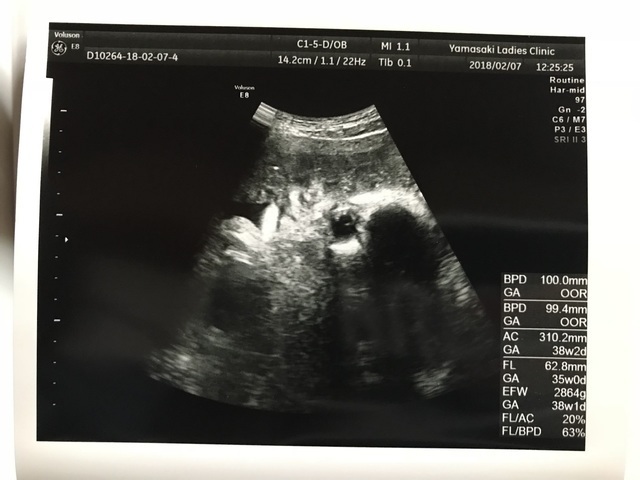

38週3日(38w3d・女の子)|silver さん(29歳)

エコー写真撮影時のエピソード:

顔が見えてしっかり目鼻立ちわかることに感動しました。 これからお姉ちゃんになる娘に準備させることができる反面今後生活スタイルをどうしていくかがんがえていくと不安ですね!